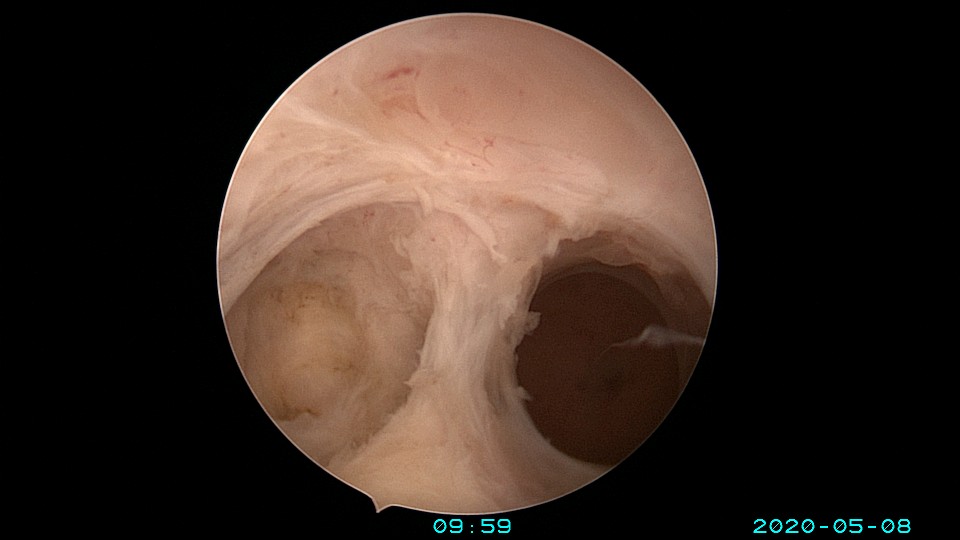

患者32岁,G10P1,剖宫产1次。2020年2月人流术后闭经2+月,2020年5月宫腔镜探查见剖宫产切口憩室,宫颈内口以上广泛封闭粘连,AFS评10分,双极电针分粘效果差,扩张宫颈管,改用双极电切分粘,恢复宫腔形态,显露双侧输卵管开口。2020年6月宫腔镜二探取球囊,宫腔形态正常,双侧输卵管开口可见。2020年10月自然妊娠,2021年2月初的某一天,在电梯里,病人的老公认出我是给他老婆做手术的医生,表达感谢之余,讲病人因先兆流产在产科保胎,情绪不稳定,甚至想终止妊娠,医生及家属努力安抚病人。2021年5月,36+3周剖宫产分娩。现37岁,G11P2。